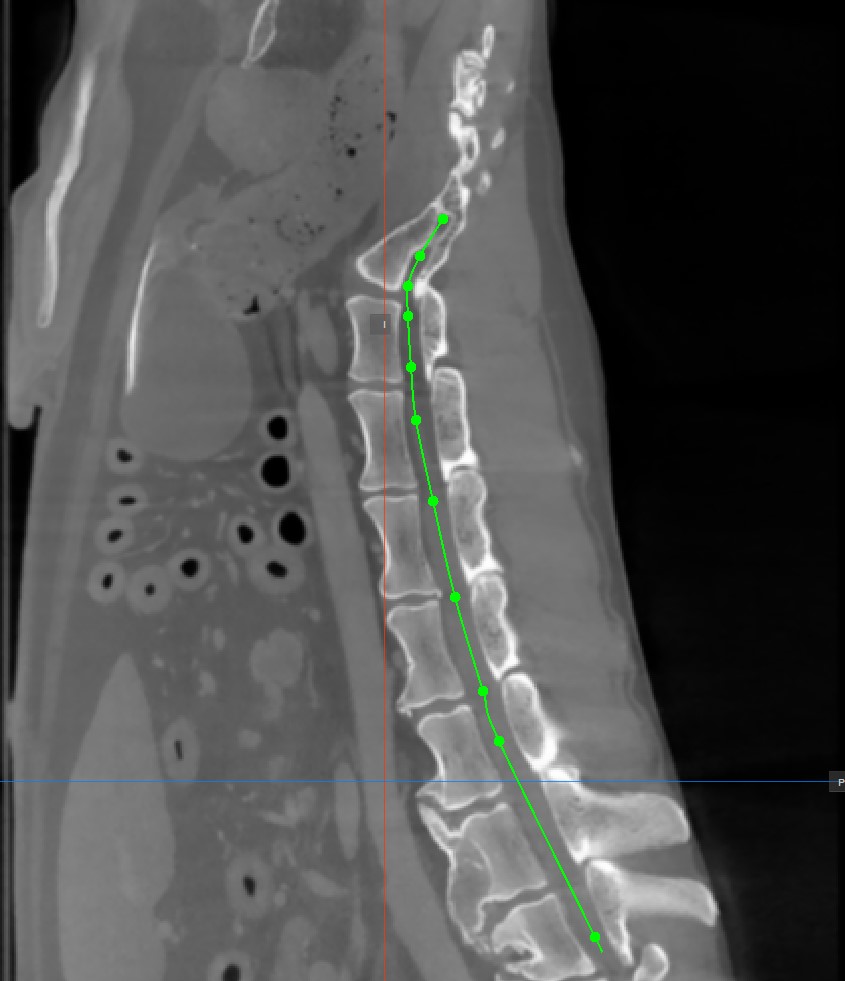

To complete the path, toggle the

Add CMPR Pointtool again, or double-click with the mouse on the image after placing the last point of the path. The path will be marked in green once it’s finalized.

Hovering over the straightened view of the CMPR path will display an orange dot on the path drawn on the MPR images, highlighting the precise location of the cursor.

Modify the CMPR path by selecting the Select/Move Item tool and assigning one of the available mouse buttons to it. Press and drag one of the base points of the path to modify its position.